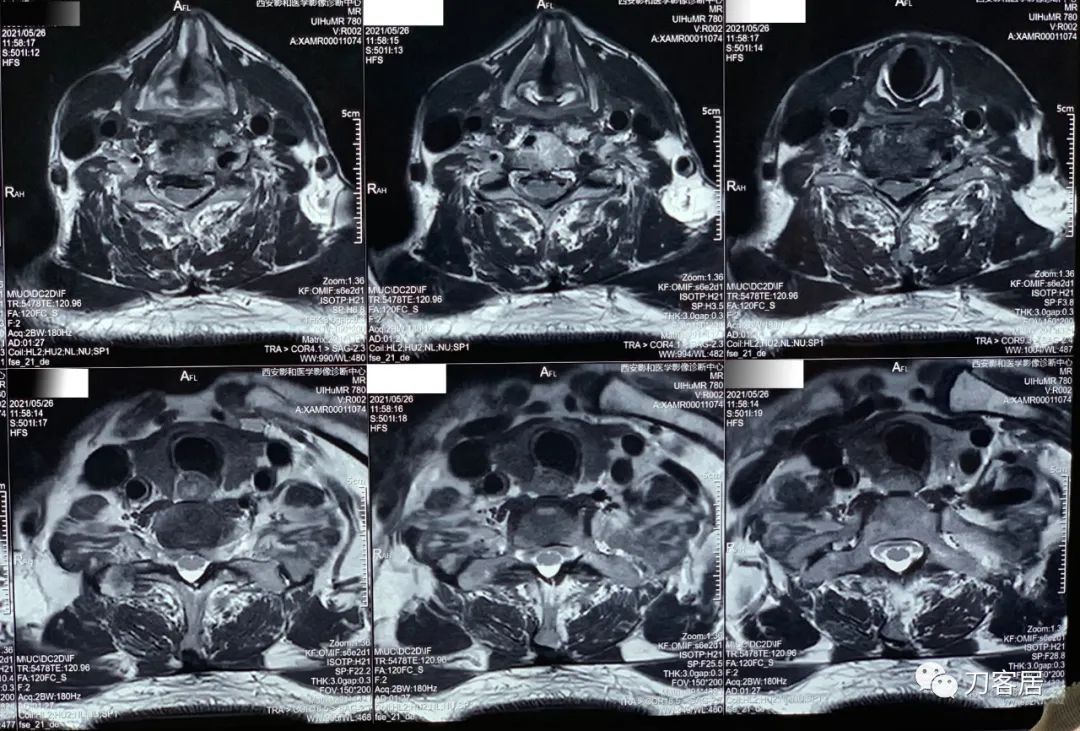

20210526-颈椎MRI经椎间盘横截面扫描。

20210526-第三方影像机构的颈椎MRI报告。